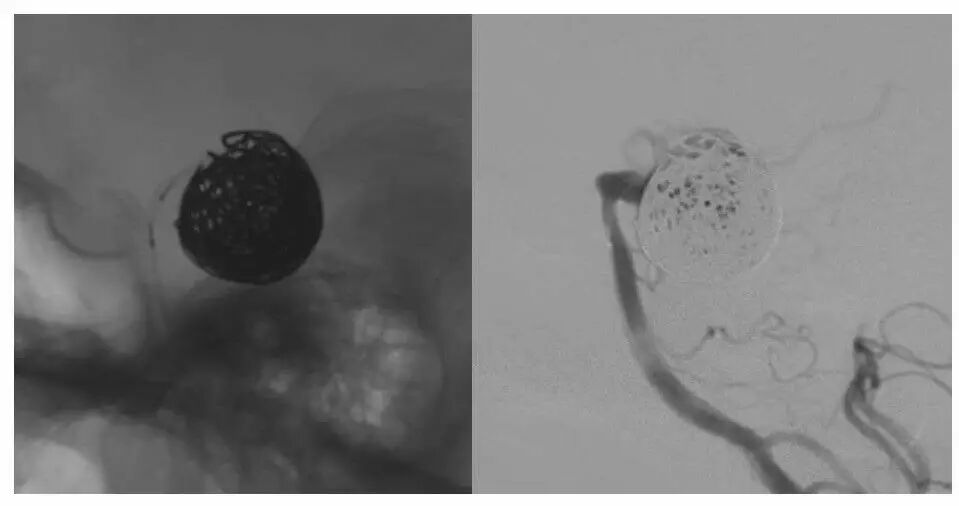

今天为大家分享的是“强生医疗CNV-神经介入专栏”第十五期,由首都医科大学宣武医院何川教授带来的“颅内动脉瘤介入治疗”精彩讲课视频及PPT,欢迎观看、阅读。文章仅代表作者个人观点,如有不同见解,欢迎同道斧正!

何川 ,首都医科大学宣武医院副主任医师,中国医师协会神经介入专业委员会常务委员,长期从事脑血管病和脊髓血管病的手术及介入治疗和相关研究工作。首都医科大学神经外科博士,师从于中国神经介入开创人凌锋教授;日本东北大学医院脑血管病治疗科博士后,师从于日本国脑血管病血管内治疗的开创者高桥教授。